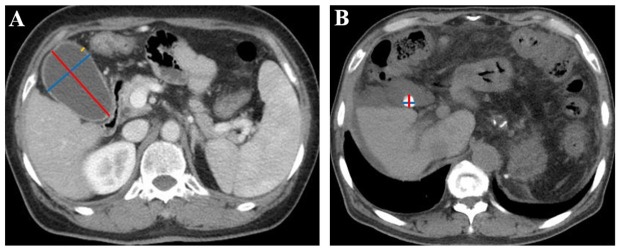

Methods: We retrospectively enrolled 206 cirrhotic patients and measured their gallbladder length and width, gallbladder wall thickness, presence of gallstones, and gallstones' length and width in axial contrast-enhanced computed tomography (CT) images. X-tile software was utilized to calculate the optimal cutoff values of these parameters for evaluating survival and hepatic decompensation events in the cirrhosis group. Their associations with survival were explored by Cox regression analyses and Kaplan-Meier curve analyses. Their associations with hepatic decompensation events were evaluated by competing risk analyses and Nelson-Aalen cumulative risk curve analyses where death was a competing event.

Results: Cirrhotic patients with gallbladder length < 72 mm had a significantly higher cumulative survival rate than those with a length of ≥ 72 mm (P = 0.049 by log-rank test), but gallbladder width, gallbladder wall thickness, presence of gallstones, and gallstones' length and width were not significantly associated with survival (P = 0.10, P = 0.14, P = 0.97, P = 0.73, and P = 0.73 by log-rank tests, respectively). Cirrhotic patients with gallbladder wall thickness < 3.4 mm had a significantly lower cumulative rate of hepatic decompensation events than those with a wall thickness of ≥ 3.4 mm (P = 0.02 by Gray's test), but gallbladder length and width, presence of gallstones, and gallstones' length and width were not significantly associated with hepatic decompensation events (P = 0.15, P = 0.15, P = 0.54, P = 0.76, and P = 0.54 by Gray's tests, respectively).

Conclusion: Changes in gallbladder length and gallbladder wall thickness, rather than gallstone parameters, may be in parallel with the long-term outcomes of cirrhotic patients.